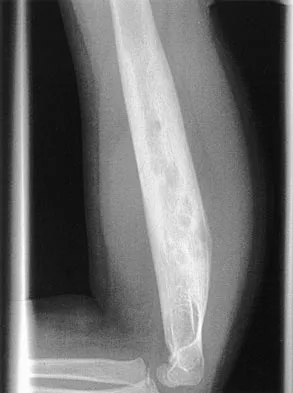

A 35-year-old man has atraumatic painless limited elbow motion. Radiographs are shown in Figures 33a and 33b. What is the most likely diagnosis?

Based on the radiographic findings, the patient has melorheostosis, a rare, benign connective tissue disorder that is characterized by a cortical thickening of bone. It produces a "dripping candle wax" appearance with dense hyperostosis that flows along the cortex. Ectopic bone formation is a consideration but is associated with injuries or burns. Bone infarcts produce intraosseous sclerosis typically affecting the distal femur with the "smoke up chimney" appearance. Infection is always a consideration but typically does not have the linear osteitis seen in melorheostosis. Juxacortical chondroma is a benign cartilage growth that arises from the capsule and may involve the underlying cortical bone but rarely the medullary canal. Campbell CJ, Papademetriou T, Bonfiglio M: Melorheostosis: A report of the clinical, roentgenographic, and pathological findings in fourteen cases. J Bone Joint Surg Am 1968;50:1281-1304.